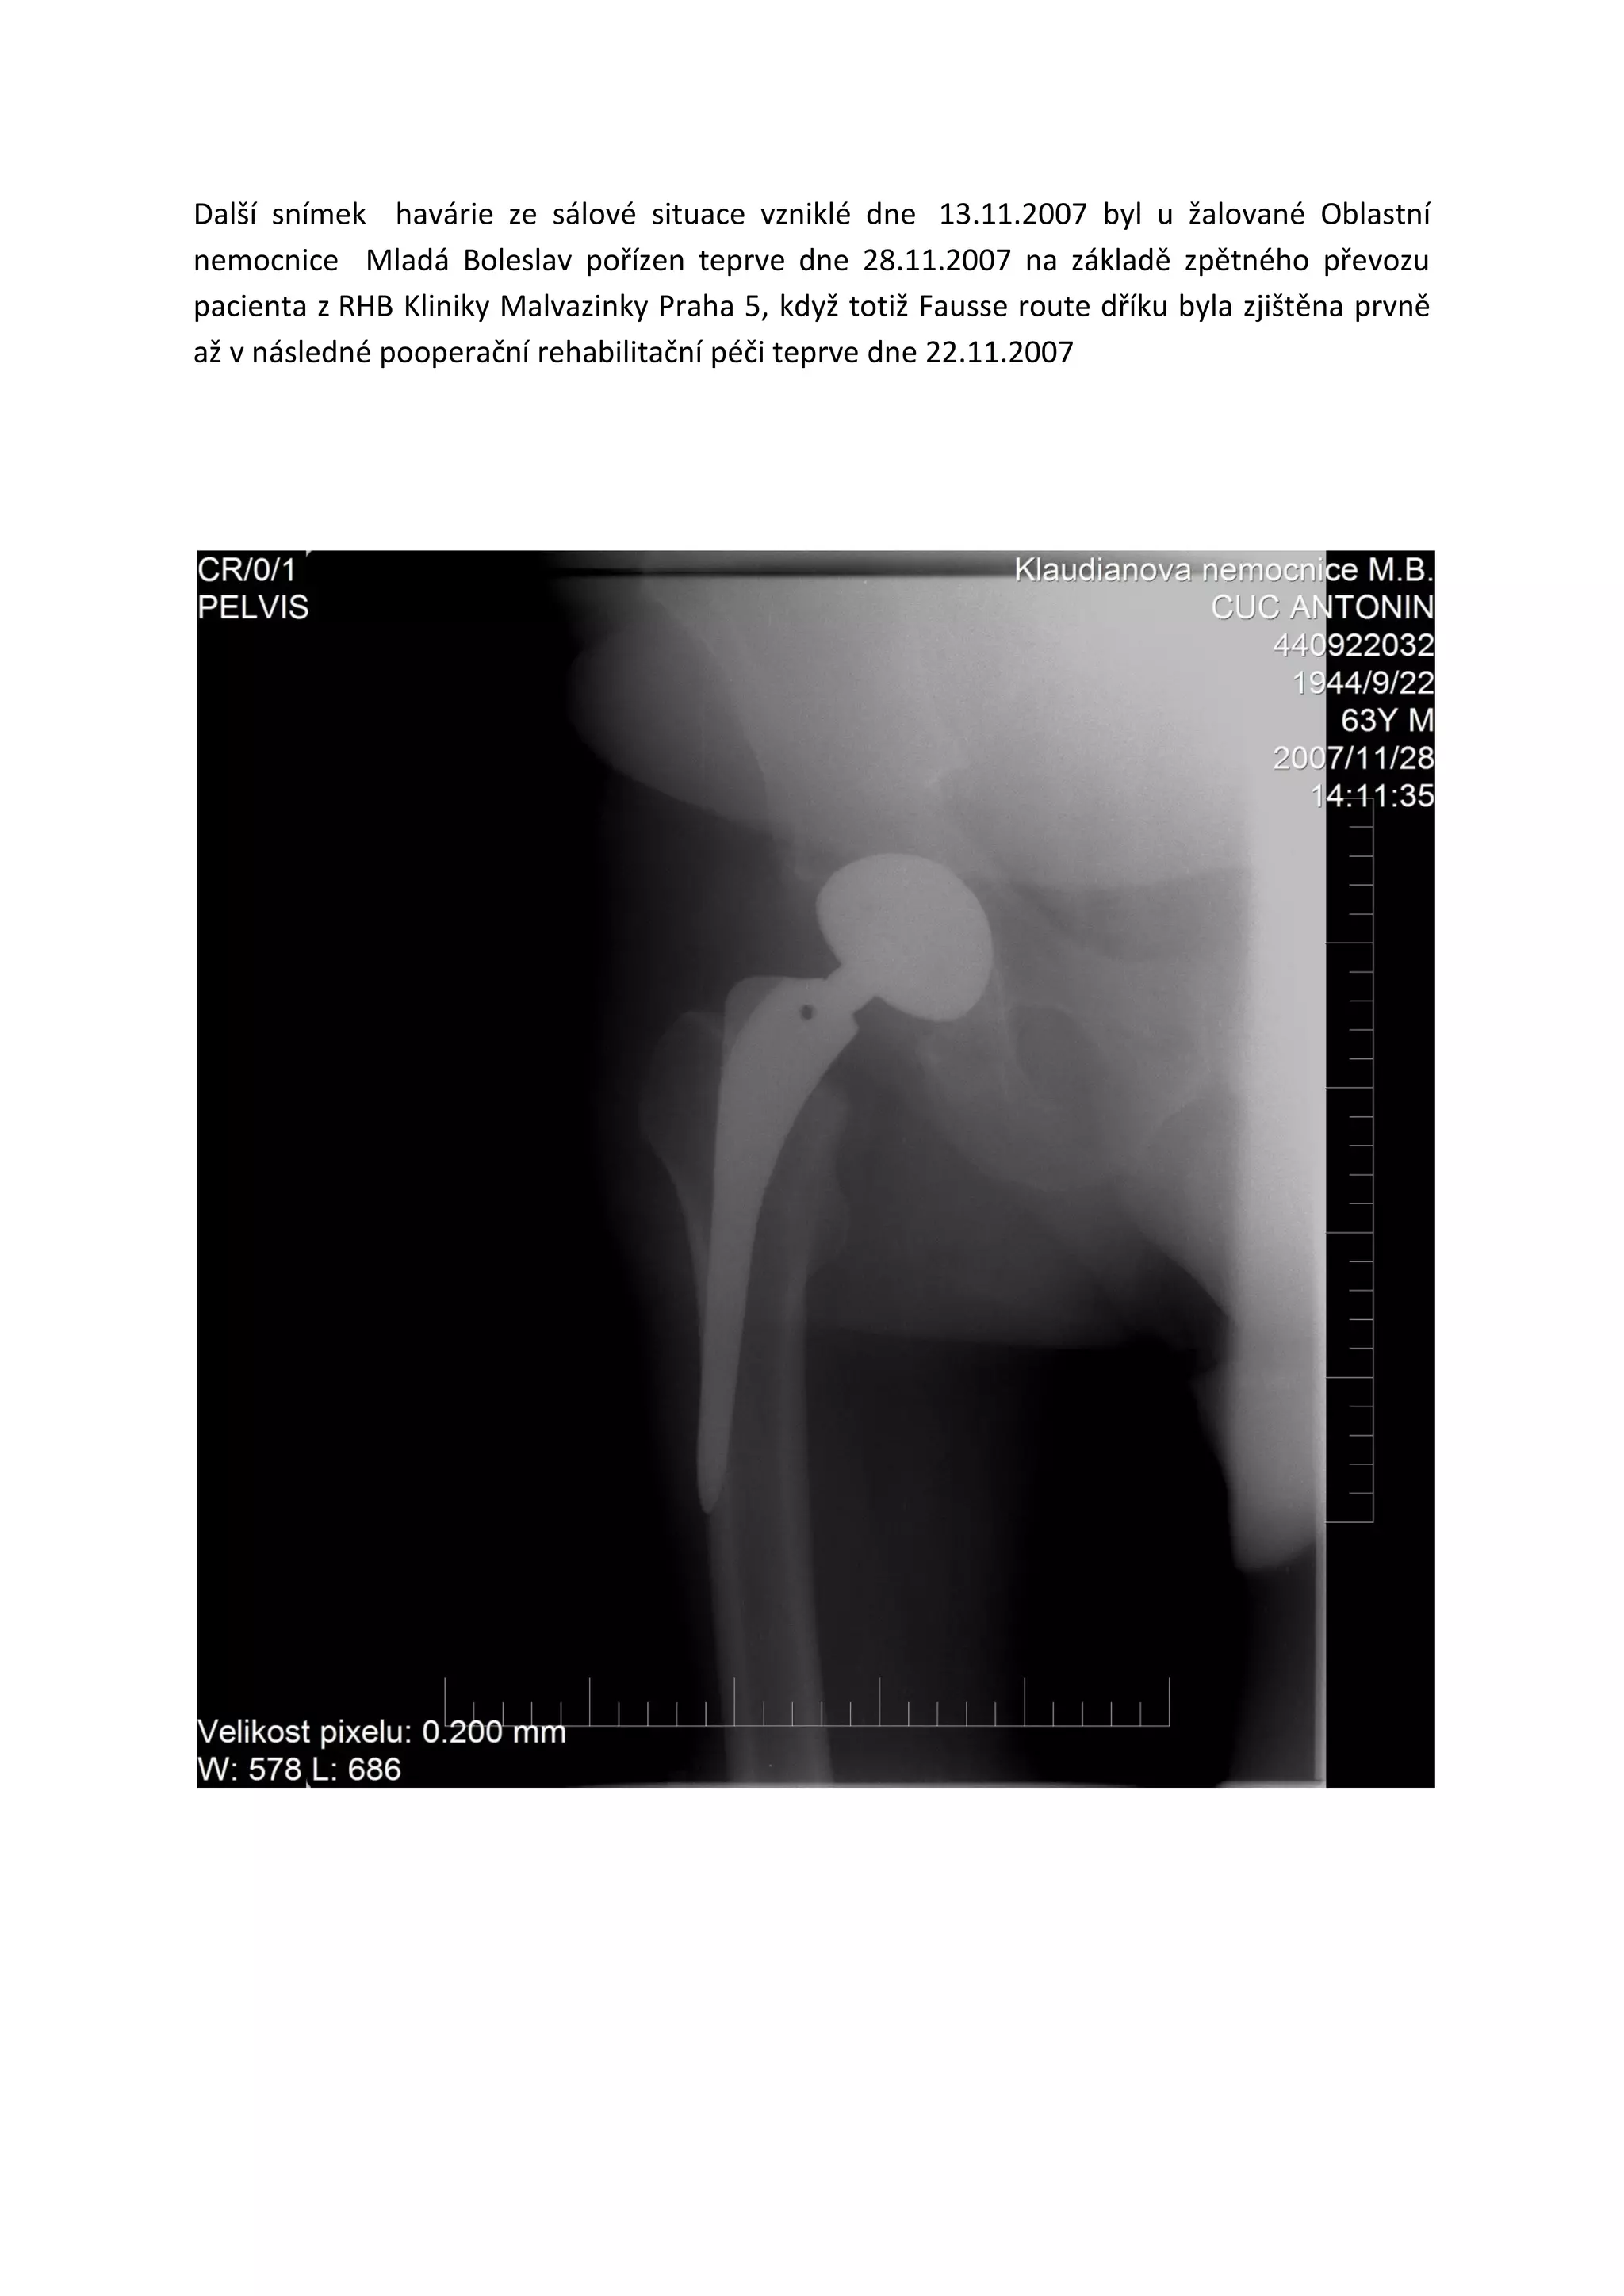

Příloha: RTG pooperační RTG snímek z 16.11.2007 a RTG snímek z 28.11.2007 po TEP kyčle,

které jednoznačně prokazují nelegálnost instalace dobře zjistitelné již pouhým přiložením

kontrolního radiologického firemního etalonu užitého dříku v měřítku na RTG z 16.11.2007 –

kde nesedí ani velikost ani tvar zobrazeného dříku, viz měření snímků na ortopedické

obrazovce v zobrazovacím systému s přesností 1 Pixel = 0,2 milimetru, viz podrobnosti

z certifikačního školení všech uživatelů v ČR pro sady TEP - BICONTACT S, necement., povrch

Plasmapore, velikosti dříku 13 mm, výrobce B. Braun. Německo

TVAR I PROFIL ZOBRAZENÉHO DŘÍKU JEDNOZNAČNĚ PROKAZUJE KŘIVOU INSTALACI DŘÍKU

VE SROVNÁNÍ S FIREMNÍM RADIOLOGICKÝM ETALONEM UŽITÉHO DŘÍKU VE STEJNÉM

MĚŘÍTKU, diagnóza Fausse route dříku měla být učiněna již z funkčního přezkoušení

smontovaného výrobku na sále 13.11.2007 podle zákona č. 22/1997 Sb. o technických

požadavcích na výrobky a o doplnění a změně některých zákonů a podle souvisejícího

Nařízení vlády č. 336/2004 Sb. Zdravotní prostředky a podle Směrnice 93/42/EHS Zdravotní

prostředky a podle implantačního zákona č. 123/2000 Sb. Zdravotní prostředky!

Další snímek havárie ze sálové situace vzniklé dne 13.11.2007 byl u žalované Oblastní

nemocnice Mladá Boleslav pořízen teprve dne 28.11.2007 na základě zpětného převozu

pacienta z RHB Kliniky Malvazinky Praha 5, když totiž Fausse route dříku byla zjištěna prvně

až v následné pooperační rehabilitační péči teprve dne 22.11.2007